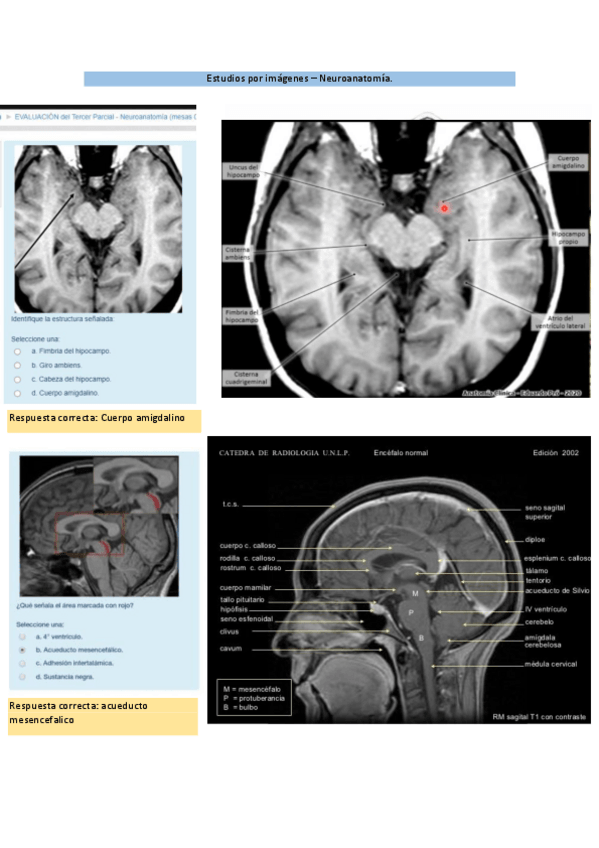

Neuroanatomía

He publicado nuevos examenes de 1º Anatomía: Neuroanatomía

Imagenes-neuro.pdf

Lab-imagenes-neuro-1.pdf

Preparados-neuro.pdf

Neuroanato-Final.pdf